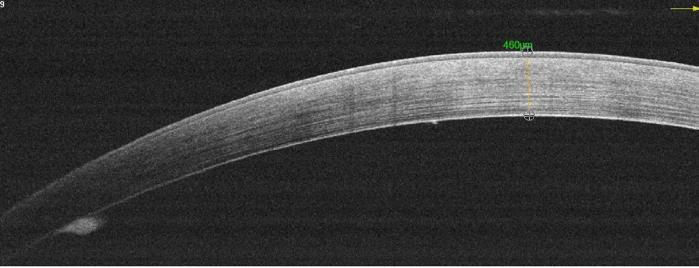

Dr Mimouni presented results of in vivo research with 64 rabbits. One-third received the implant seeded with human corneal endothelial cells, one-third the scaffold alone, and the remainder underwent sham surgery. All underwent unilateral descemetorhexis of the right eye. Subacute (4-week) and chronic (26-week) endpoints were assessed.

“In the sham group that underwent descemetorhexis only, we found severe corneal oedema followed by stromal scarring. In the scaffold-only group we saw that most animals developed subepithelial fibrosis and that there was a 46% detachment rate, with all those animals developing severe oedema. The overall average central corneal thickness was 630 microns. In the PVEK group, at 6 months we saw a 16% detachment rate with a significantly lower average central corneal thickness of 391 microns,” he reported.

• Sham (control 1)

– Severe corneal edema

– Stromal scarring

– Average CCT: 761µm

• Scaffold only (control 2)

– Subepithelial fibrosis

– 6 mo. detachment: 46%

– Average CCT: 630µm

• PVEK

– 6 mo. detachment: 16%

– Average CCT (attached): 391µm

Animal 8046

CCT: 889µm

Animal 8023 CCT: 460µm

Animal 8085 CCT: 386µm